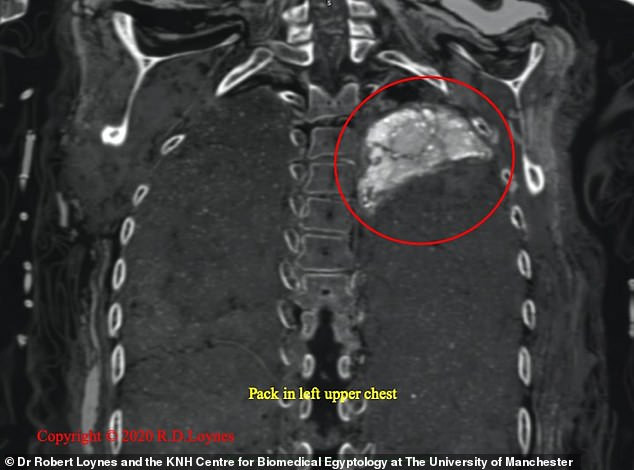

Takabut qua đời khi khoảng 20 tuổi bởi một vết đâm ở sau lưng gần vai trái. Vào năm 1834, xác ướp Takabut được đưa đến Ireland.